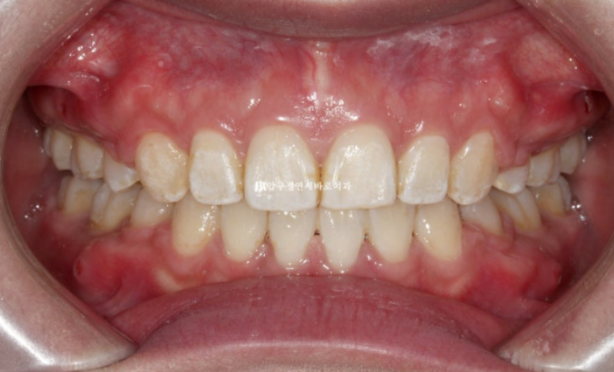

그리고 치료시작 1년 7개월째에 드디어 교정을 마치고 장치를 뗐습니다.

24.09

중심선이 맞아졌고

교합도 좋습니다.

23.02~24.09

치료기간은 총 1년 7개월입니다.

보통의 발치교정은 2년정도라고 하지만 20대 초반까지 젊은 환자분은 1년 6개월~2년 사이 정도 걸리는 것이 가장 많습니다.